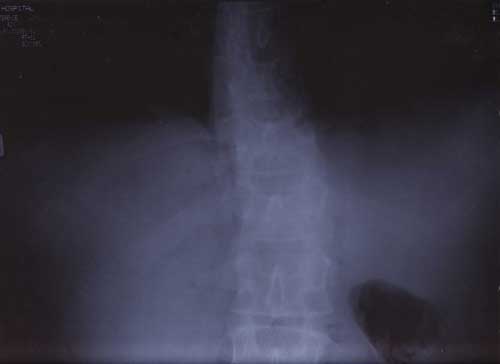

21st January 2000